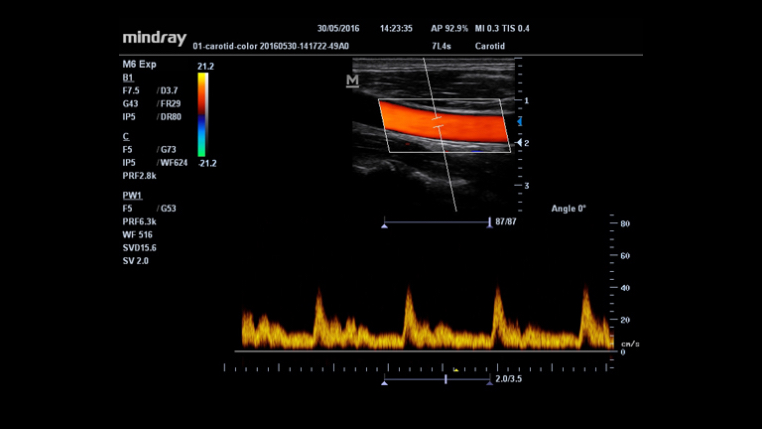

Maximum 8 times tasking for one transmitted beam, resulting in excellent time resolution and higher frame rate.

An innovative technology to better visualize tiny vessels and complex flow patterns, based on Mindray's exclusive processing algorithm.

Auto measurement of anterior and posterior wall thickness providing accurate carotid status.

MindrayŌĆÖs unique function: Continuously track the color flow and optimize the best Color box position and angle in real time scanning